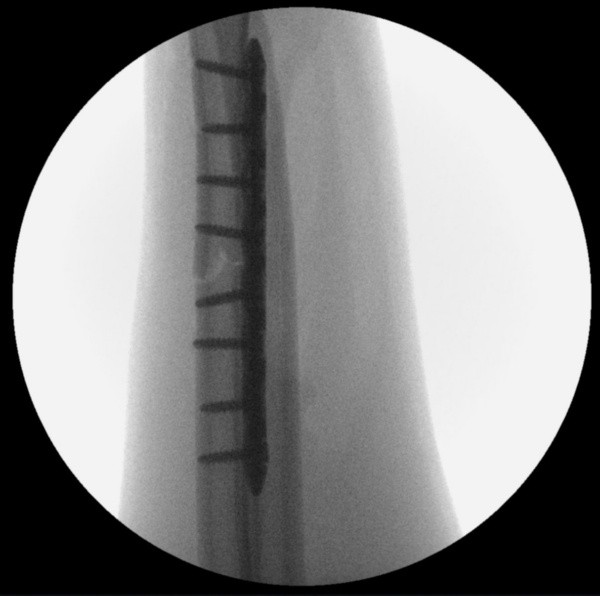

VEJA IMAGENS DA TOMOGRAFIA PRÉ-OPERATÓRIA E DAS RADIOGRAFIAS PÓS-OPERATÓRIAS:

Após a cirurgia, com as placas e parafusos (Foto: Divulgação)